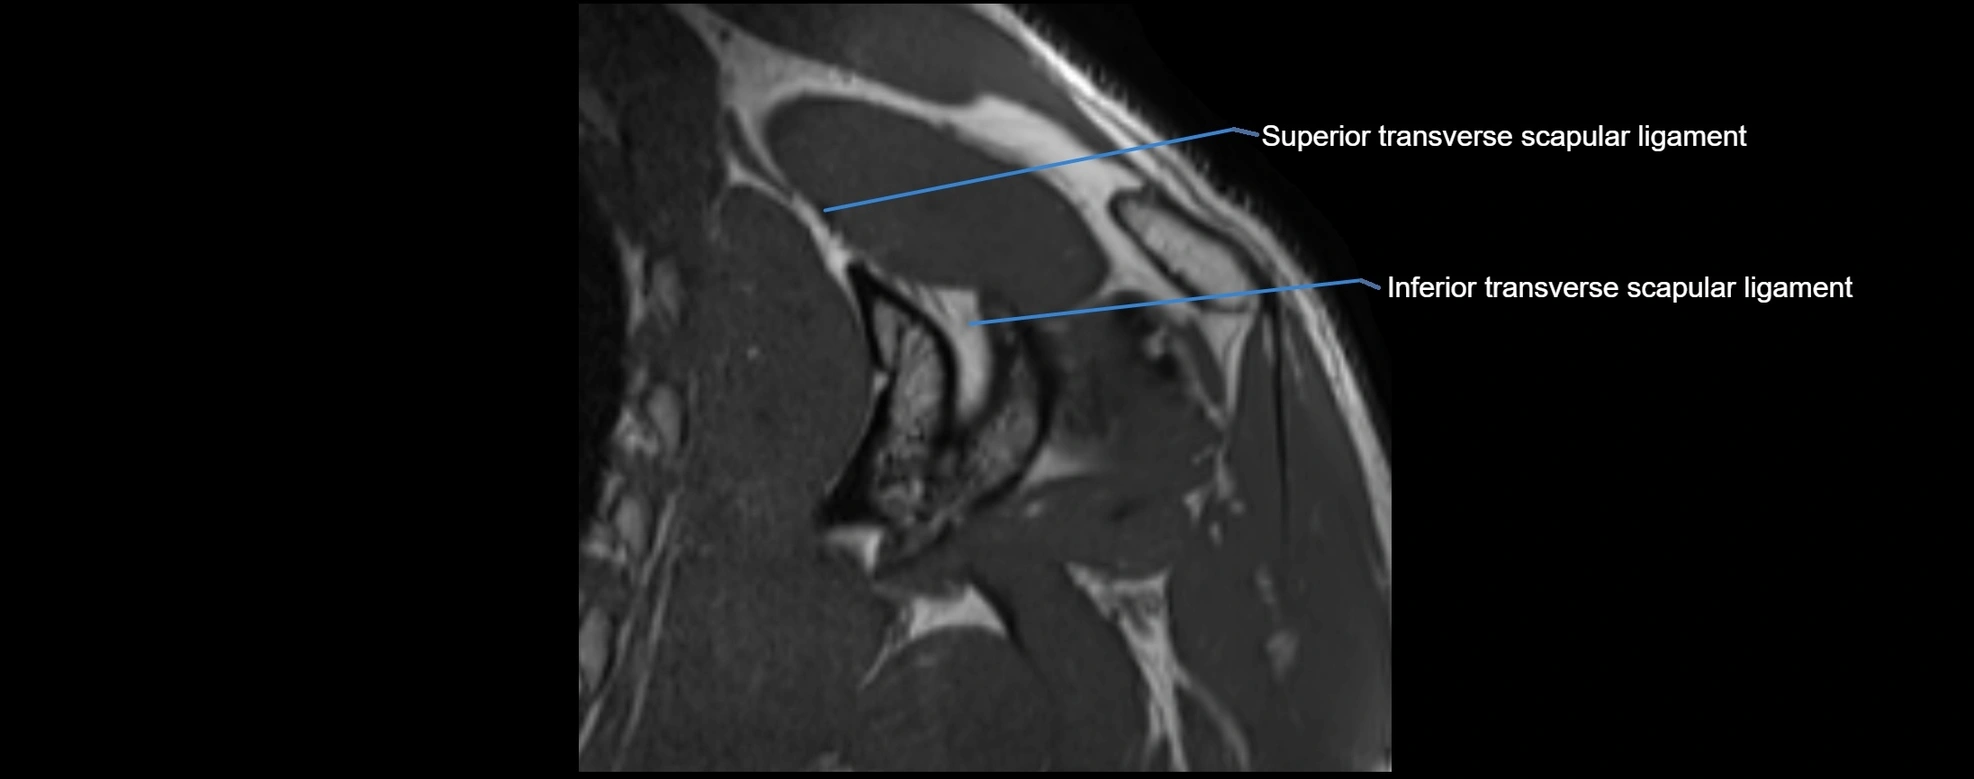

CT image

image